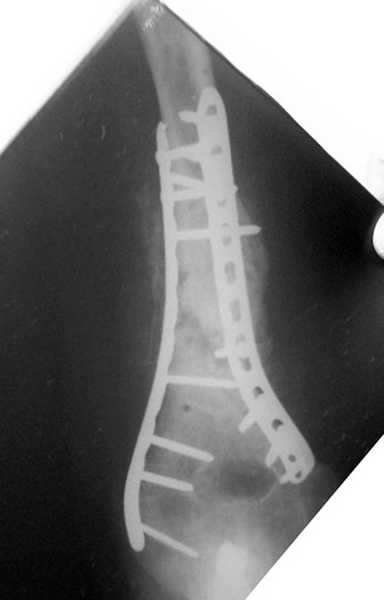

На примере два случая, извиняюсь за качество снимков, снимки и случаи из бывшего союза.

Первая больная с "успехом" была прооперирована 6 раз различными методами открытого и закрытого

остеосинтеза, включая то, что в Кисловодске заезжим австралийским "кудесником" на ложный сустав уложена скорлупа от страусиновых яиц. Последняя операция одиноким локинг плейт в одной из клиник.

Через год по поводу тех же проблем сделали ревизию, оригинальную пластину оставили как есть, только укрепили добавлением еще одной пластины и сделали костную пластику.

Через два месяца увидели признаки консолидации.

Второй случай, также после множественных операций:

пластина, аппарат, серкляж и парез нерва.

Также ревизия, из-за низкого состояния доступ был

сделан через остеотомию локтевого отростка.

Ложный сустав фиксирован двумя локинг плейт с

аутокостной пластикой, также через два месяца увидели признаки консолидации.

Движение в суставе разрешили в две недели.